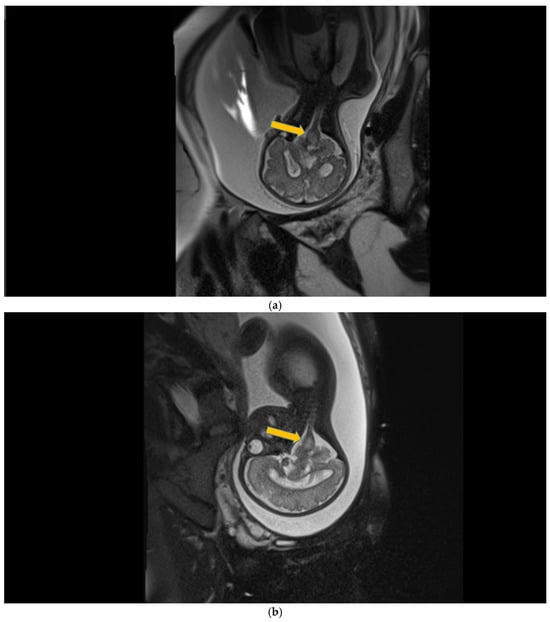

Case 5 involved a 35-week gestational age newborn who presented with birth asphyxia and required resuscitation after delivery, which involved a balloon and mask and then a balloon and laryngeal mask, and afterwards mechanical ventilation in the NICU (Neonatal Intensive Care Unit) with SIMV/IPPV (synchronized intermittent mandatory ventilation/invasive positive pressure ventilation), who was antenatally diagnosed through MRI with subacute polyhydramnios and ventriculomegaly due to a suspected medulla oblongata tumor (Figure 5a).

Figure 5.

(a,b) MRI—T2 sequence. Sagittal view. Antenatal. Yellow arrows indicate the place of the suspected tumor (personal image collection). (c) Cranial ultrasound. Sagittal view. Up—enlarged left ventricle. D1—thamalo-occipital distance. Down—enlarged right ventricle. D1—thalamo-occipital distance (personal image collection). (d) Cranial ultrasound. Sagittal view. Enlarged third ventricle. Fourth ventricle is normal. D1, D2—measurements of the third ventricle (personal image collection). (e) Cranial ultrasound. Transtemporal view. Enlarged third ventricle. Sylvian aqueduct is not visible. D1—measurement of third ventricle. LV AH—lateral ventricle anterior horn. LV OH—lateral ventricle occipital horn. V 3—third ventricle (personal image collection).

After stabilization, the cranial ultrasound exam revealed enlargement of the lateral ventricles and third ventricle, with a normal fourth ventricle. There was no visualization of the Sylvian aqueduct, which raised the suspicion of aqueduct atresia or stenosis (Figure 5c–e). There was no improvement seen in the cranial ultrasound examinations that followed.